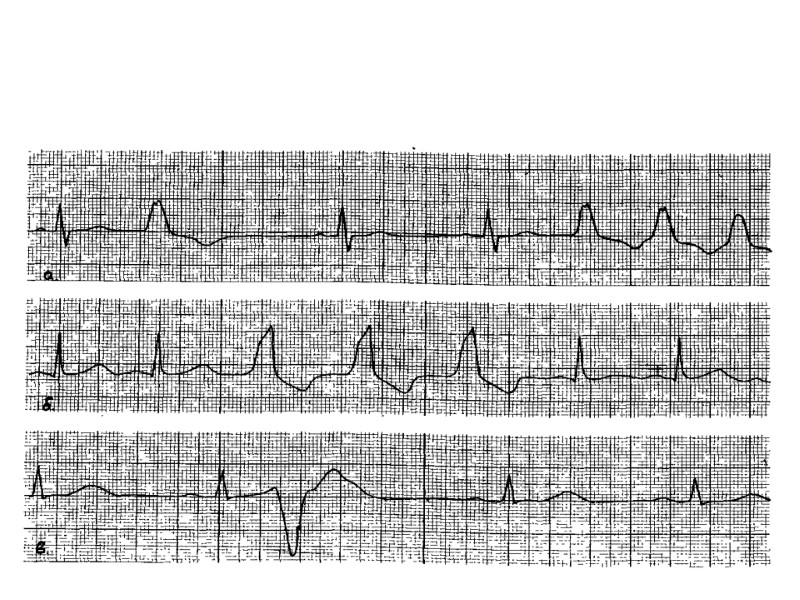

Выделяют три основных типа нарушения диастолической функции ЛЖ – Гипертрофический Псевдонормальный Рестриктивный.

В норме типичные показатели митрального кровотока в диастолу имеют два пика: волна Е и волна А. Первая отражает раннюю (Е) фазу заполнения ЛЖ, вторая — предсердный (А) компонент диастолического заполнения ЛЖ. В качестве основных критериев используются также отношение Е/А и время замедления раннего трансмитрального потока. При необходимости определяются дополнительные показатели, такие как продолжительность фазы изоволюметрического расслабления, фракция предсердного наполнения, отношение VTIE/VTIA, отношение S/D и др. При нарушении диастолической функции ЛЖ эти показатели изменяются